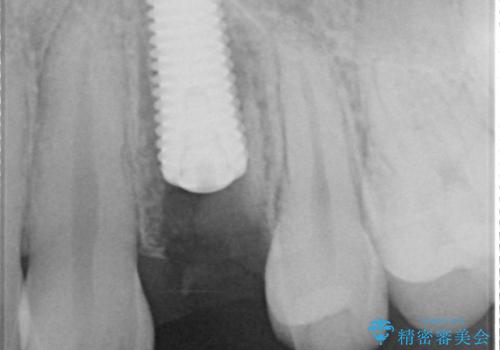

- 以前他院で、左上小臼歯(前から4番目)の虫歯治療を受けた患者様が、歯の根元から歯が折れてしまったことを主訴に来院されました。

他院では「抜歯が必要」と診断されており、「どうせ抜歯になるなら、矯正治療でスペースを閉じられないか」というご相談でした。

左上の小臼歯は健全な歯質が薄く将来的な歯根破折リスクが高く予後不良で、叢生(歯並びの乱れ)はほとんどなくご本人も歯並び自体は気になっていないという状態でした。

左上小臼歯を抜歯し、矯正治療でスペースを閉じる方法と左上小臼歯を抜歯し、抜歯即時インプラントを行う方法、保存療法を行う方法の治療期間、費用、メリット・デメリットについて説明したうえで治療期間をできるだけ短くしたいという希望があったため抜歯即時インプラント治療を選択されました。